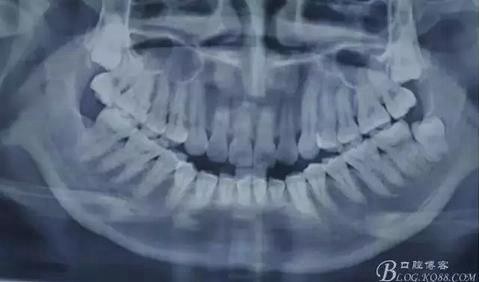

患者、李xx、女、21歲。主訴:因正畸需要拔出上頜埋伏智齒。??茩z查:18、28均未萌出,捫及上頜結(jié)節(jié)后份,未有明顯隆起。全景片檢查:18、28高位近中埋伏阻生,牙冠近鄰17、17根部。診斷:高位近中埋伏阻生。術(shù)前與患者溝通,有上頜竇穿通風(fēng)險(xiǎn)?;颊吆炐g(shù)前知情同意書(shū)。

圖1.術(shù)前全景片影像檢查:18、28高位近中阻生,牙冠均緊鄰17、27牙頸部,牙根近鄰上頜竇。